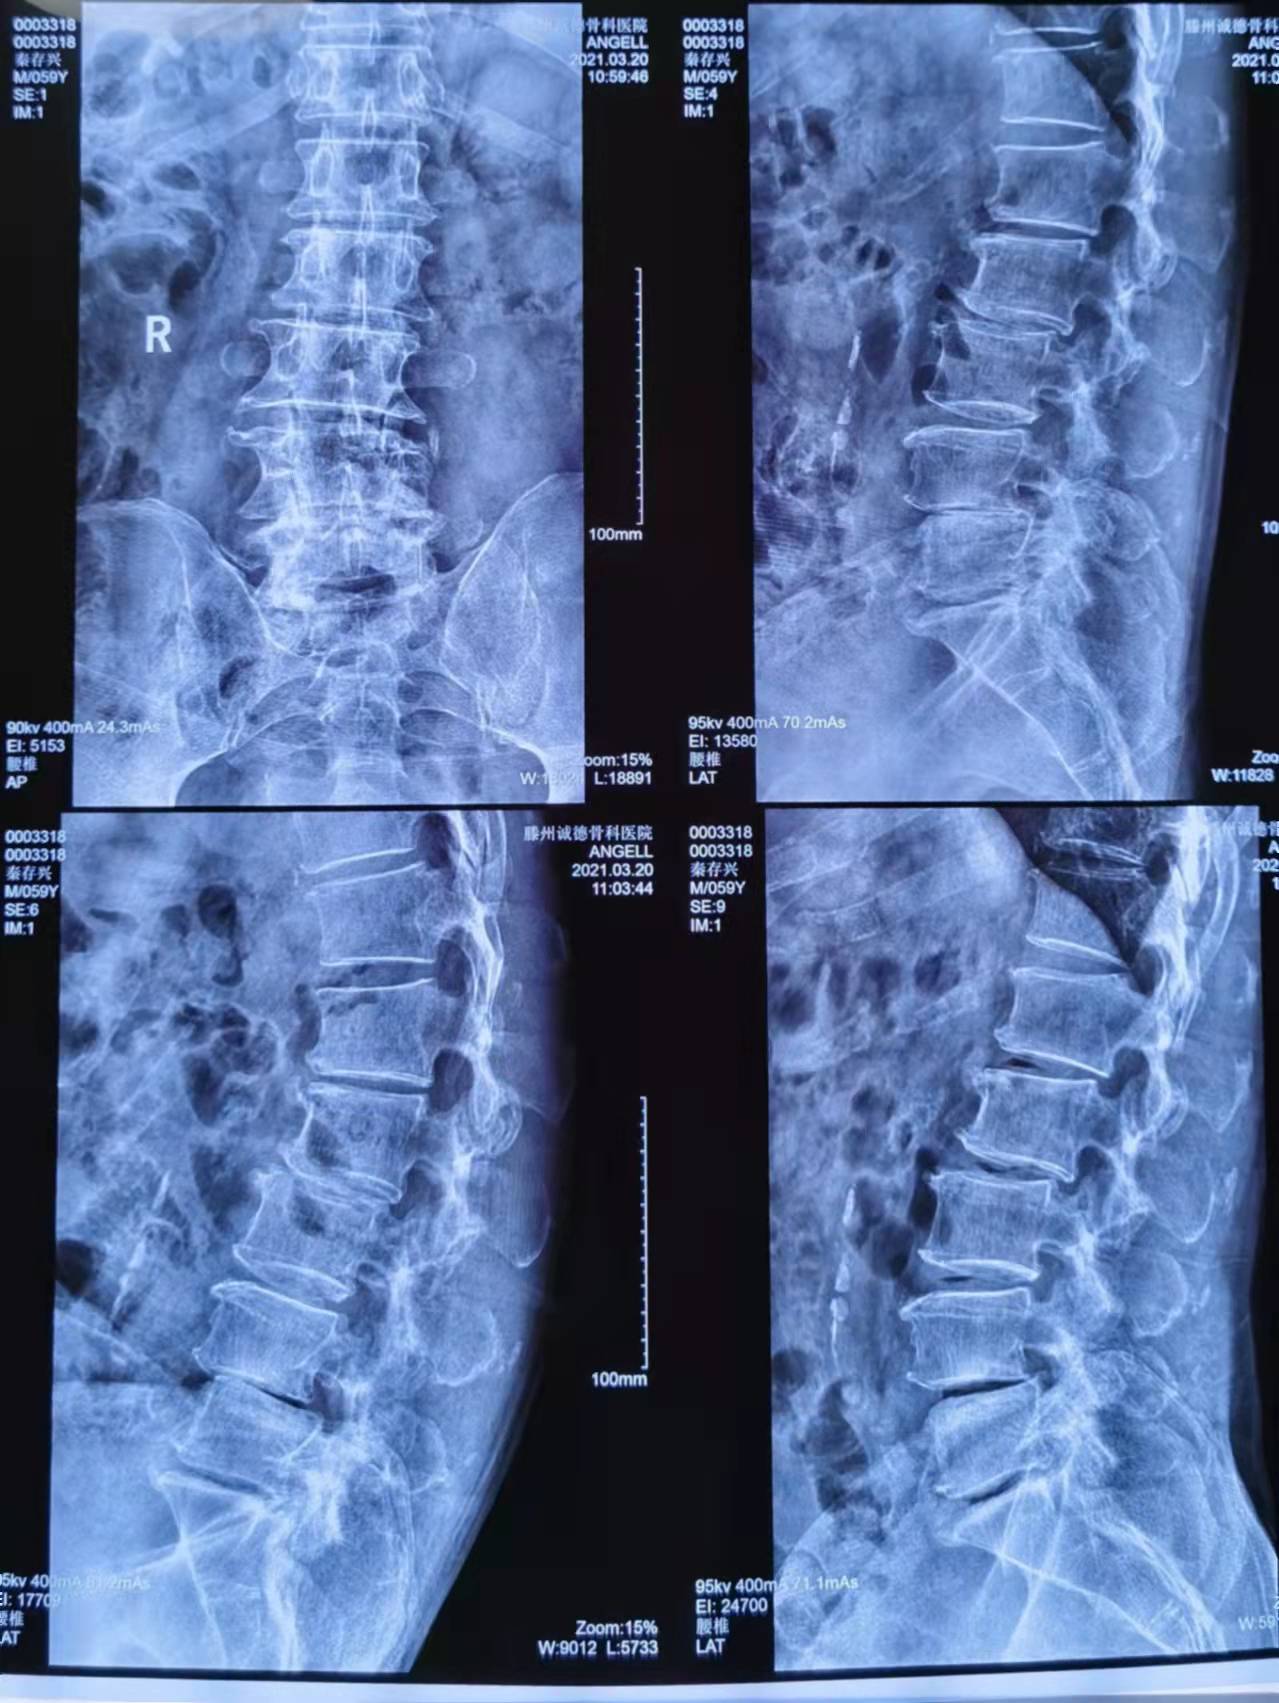

患者秦存興,男,59歲,腰痛多年勞累后加重,近一年來感腰痛伴雙側(cè)臀部、左大腿外側(cè)、小腿外側(cè)及右足麻木,行走50米后即感雙下肢疼痛劇烈,病痛的折磨給患者的生活帶來了很大的痛苦,讓他對未來失去了信心。來到誠德骨科醫(yī)院

經(jīng)查體、X片、CT及核磁共振檢查后確診為腰椎管狹窄癥,腰椎退變性滑脫,與患者充分溝通后決定行腰1-腰5減壓植骨內(nèi)固定術(shù)